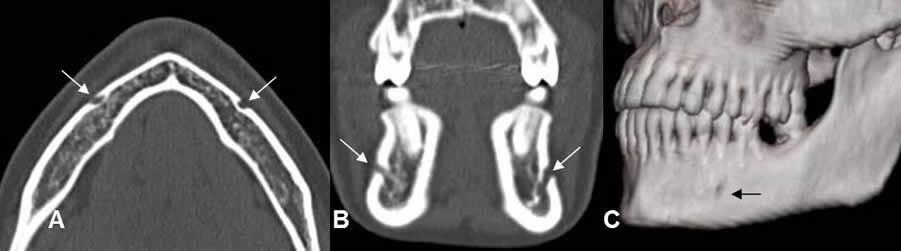

Fig 9. Canal mandibular normal.

A: TAC axial, B: TAC coronal y C: TAC reconstrucción 3D. Orificio de salida del canal mandíbular, entre el 1º y 2º premolar.